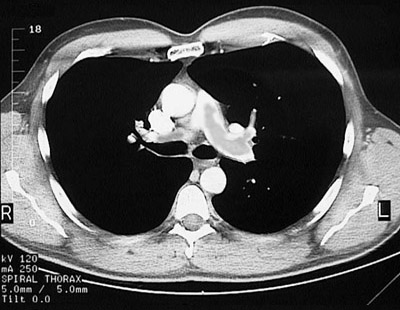

In most cases the most definitive, readily available study for diagnosis of pulmonary thromboembolism is a chest CT scan. A saddle pulmonary embolus and extension into the right pulmonary artery is seen here.